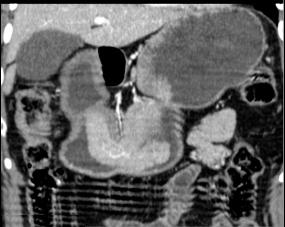

Image d'une

tumeur epitheliale de estoma . Sa taille est plus

marquee situe a la face posterieure de estomac , sa

bord est net , polylobulaire intraluminale et

hyperdense non homogene . Paroie de l;estoma reste

normale ( image TDM en coupe axiale ) |

Meme cas en coupe coronale (

frontale ) . la tumeur situe a la portion horizontal

region antral de l'estomac |